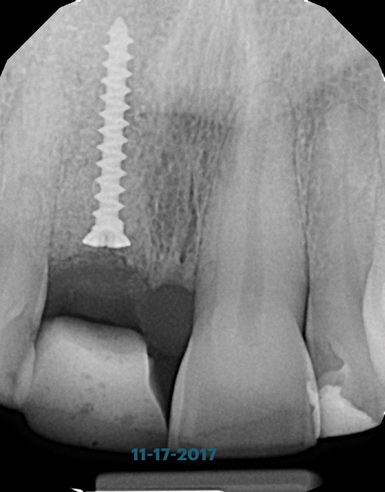

(21.) Postoperative periapical radiograph taken immediately after placement of the implant at site No. 8 demonstrating implant positioning centered with the planned location of the gingival zenith and two titanium alloy tacks that were used to stabilize the resorbable membrane apically.

Figure 21

Prior to the initiation of the surgery, the surgical guide was tried in to confirm proper seating and stability (Figure 15). A flapless approach was not considered because the need for further bone grafting at the time of implant placement had been anticipated through the digital planning. A slightly palatal crestal incision was made, followed by two vertical incisions on the mesial and distal aspects of the edentulous site in order to preserve the papilla and avoid additional esthetic compromise to the anterior sextant. Next, a full-thickness flap was elevated to facilitate removal of the tenting screw and permit visualization of the buccal plate (Figure 16). A standard guided protocol was followed to place the implant, and its final position mirrored that of the digital plan. As predicted, the prosthetically driven implant position resulted in an insufficient buccal plate (Figure 17); therefore, additional guided bone regeneration was performed to reinforce the area and prevent future breakdown (Figure 18 and Figure 19). Making periosteal incisions could have compromised the blood supply to the flap, so instead, it was stretched in order to achieve tension free coronal advancement.31The flap was secured utilizing horizontal mattress sutures with additional supportive interrupted sutures to ensure primary closure (Figure 20). An immediate postoperative periapical radiograph (Figure 21) and CBCT scan (Figure 22) were taken, demonstrating a final implant position centered with the planned location of the gingival zenith.